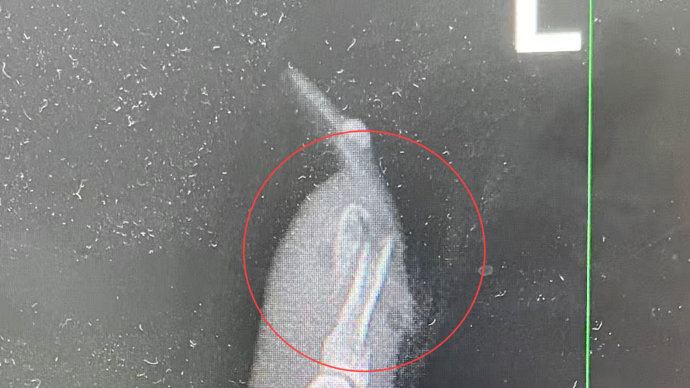

“左手食指指骨骨折,甲床破裂,部分甲床外露,需要手术修复。”接诊的曹立副主任医师检查后作出诊断,并当即对其做了指骨骨折闭合复位内固定术。

王小姐术前的X光影像